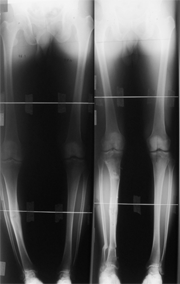

さらに股関節や膝関節だけでなく、怪我の影響や先天的な問題、あるいは関節リウマチなどで、スネや足首、足部の変形(外反母趾など)や痛みが進んで困っている場合にも、骨切り術や創外固定器を用いて変形を矯正することができます。

さらに四肢の重症外傷や外傷後の変形治癒・偽関節(骨折した骨がくっつかない)症例にイリザロフ創外固定器を使用しています。この方法は、正確な矯正、確実な骨癒合、骨長調節が可能で、複雑な変形や骨欠損のある場合にも対応が可能です。そして何よりも、今までの方法に比べ強固な固定性のために、すぐに歩く練習が可能で、入院期間も短く、社会復帰が早いことが分かっています。